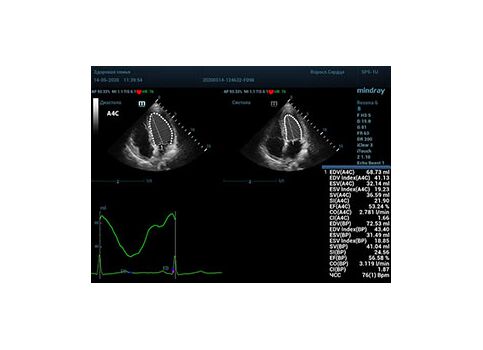

С появлением В режима реализовалась возможность визуализации всех сегментов миокарда из парастернальных и апикальных сечений. Метод Teicholtz в широкой практике сменился методом дисков. Метод дисков, или метод Simpson, позволяет разбить левый желудочек на 20 дисков, с расчетом объема каждого из них. Используя 2 перпендикулярных сечения, апикальные двух и четырех камерное, мы приближаемся к значению реального объема левого желудочка. Исследователь обводит интерфейс эндокард – кровь в фазу диастолы и фазу систолы. Линия простирается от кольца митрального клапана и до кольца митрального клапана, четко разграничивая объем желудочка от предсердия. Для достоверного изменения необходимо использовать ЭКГ канал.

Что могут предложить современные приборы? Приборы нашего времени являются мощными вычислительными машинами, способными обрабатывать полученную информацию даже без помощи человека. Система автоматического вычисления фракции выброса – AUTO EF на

приборах серии Resona компании Mindray сделает все за вас. За пару секунд прибор сам отыщет нужную фазу сердечного цикла и произведёт измерение и расчеты, а также покажет график изменения объема в сердечном цикле. От Вас требуется только получить качественное 4С и 2С сечение. Впрочем, прибор всегда оставляет возможность коррекции, если доктор имеет свое мнение на расположение точек планиметрии или момента измерения по ЭКГ каналу.